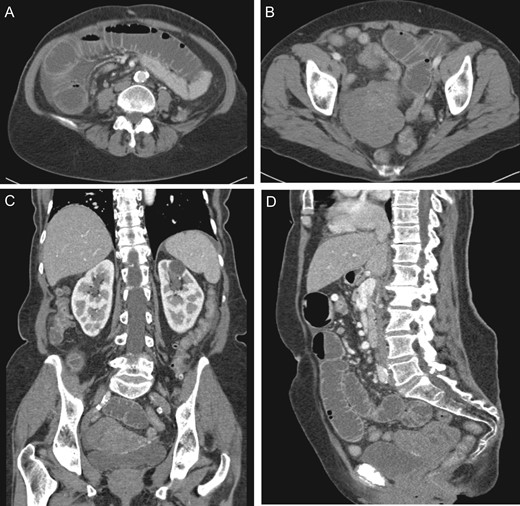

A 74-year-old G3P3003, postmenopausal female with an incidental 7.6 cm lobulated pelvic mass seen on prior computed tomography (CT) for flank pain. Follow-up ultrasound (US) was consistent with a 5.9 × 3.4 × 2.9 cm3 uterus with 4–5 mm endometrium and 7.5 × 4.9 × 5.5 cm3 hypoechoic solid mass on the posterior aspect of the uterus with significant internal vascular flow (Fig. 1). The mass was noted to be separate from the uterus without evidence of free fluid or ascites; however, a normal right ovary was unable to be identified. No tumor markers were obtained at that time; however, she was counseled about her pelvic mass and referred to gynecologic oncology for further management. At that time, she denied any history of unintentional weight loss, fatigue, postmenopausal bleeding, pelvic pressure or pain, changes in diet, bloating or changes in bowel or urinary habits.

(A) Uterus measuring 5.9 × 3.4 × 2.9 cm3 with heterogeneously hypoechoic solid mass, measuring 5.5 × 4.9 × 7.5 cm3 right aspect of the uterus. (B) Color Doppler flow analysis with significant internal vascular.